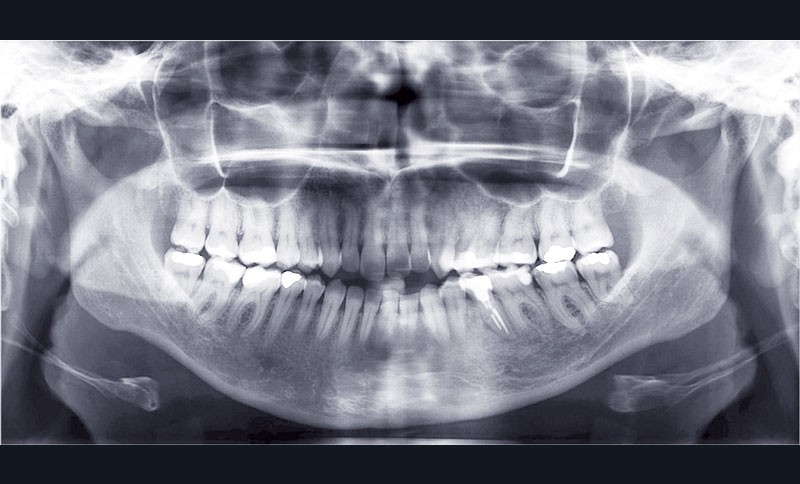

Les empreintes ont été réalisées en sillcone wash technique et adressées au laboratoire Insignia. Actuellement, nous réalisons ces empreintes à l’aide de la caméra intra-orale Lythos et la fiche patient est initialement créée sur la caméra. Le transfert des empreintes au laboratoire est immédiat et le risque d’erreurs considérablement réduit (fig. 4 à 6).